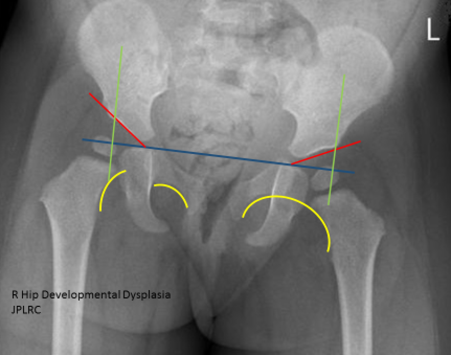

Developmental Hip Dysplasia Ddh

Developmental dysplasia of the hip. Two tests are performed called the. During the examination an X-ray machine sends a beam of radiation through the pelvic bones and hip joints and an image is recorded on a computer or special film.